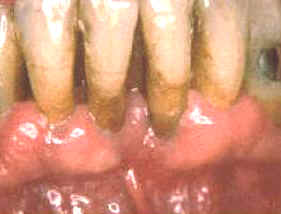

La imagen muestra

la condición 3 semanas después del tratamiento. La curación ha

progresado pero algo más de placa puede observarse en comparación al

fotograma anterior. El paciente ha reducido el control químico de placa

bacteriana por el sabor

amargo del cclorhexidine. Para

conservar a menudo el resultado del tratamiento es necesario que el

paciente realice el control químico de la placa bacteriana a intervalos

regulares y debe mantener un correcto cepillado dental. El éxito del

tratamiento depende fundamentalmente de la colaboración del paciente en

su hábito higiénico. |